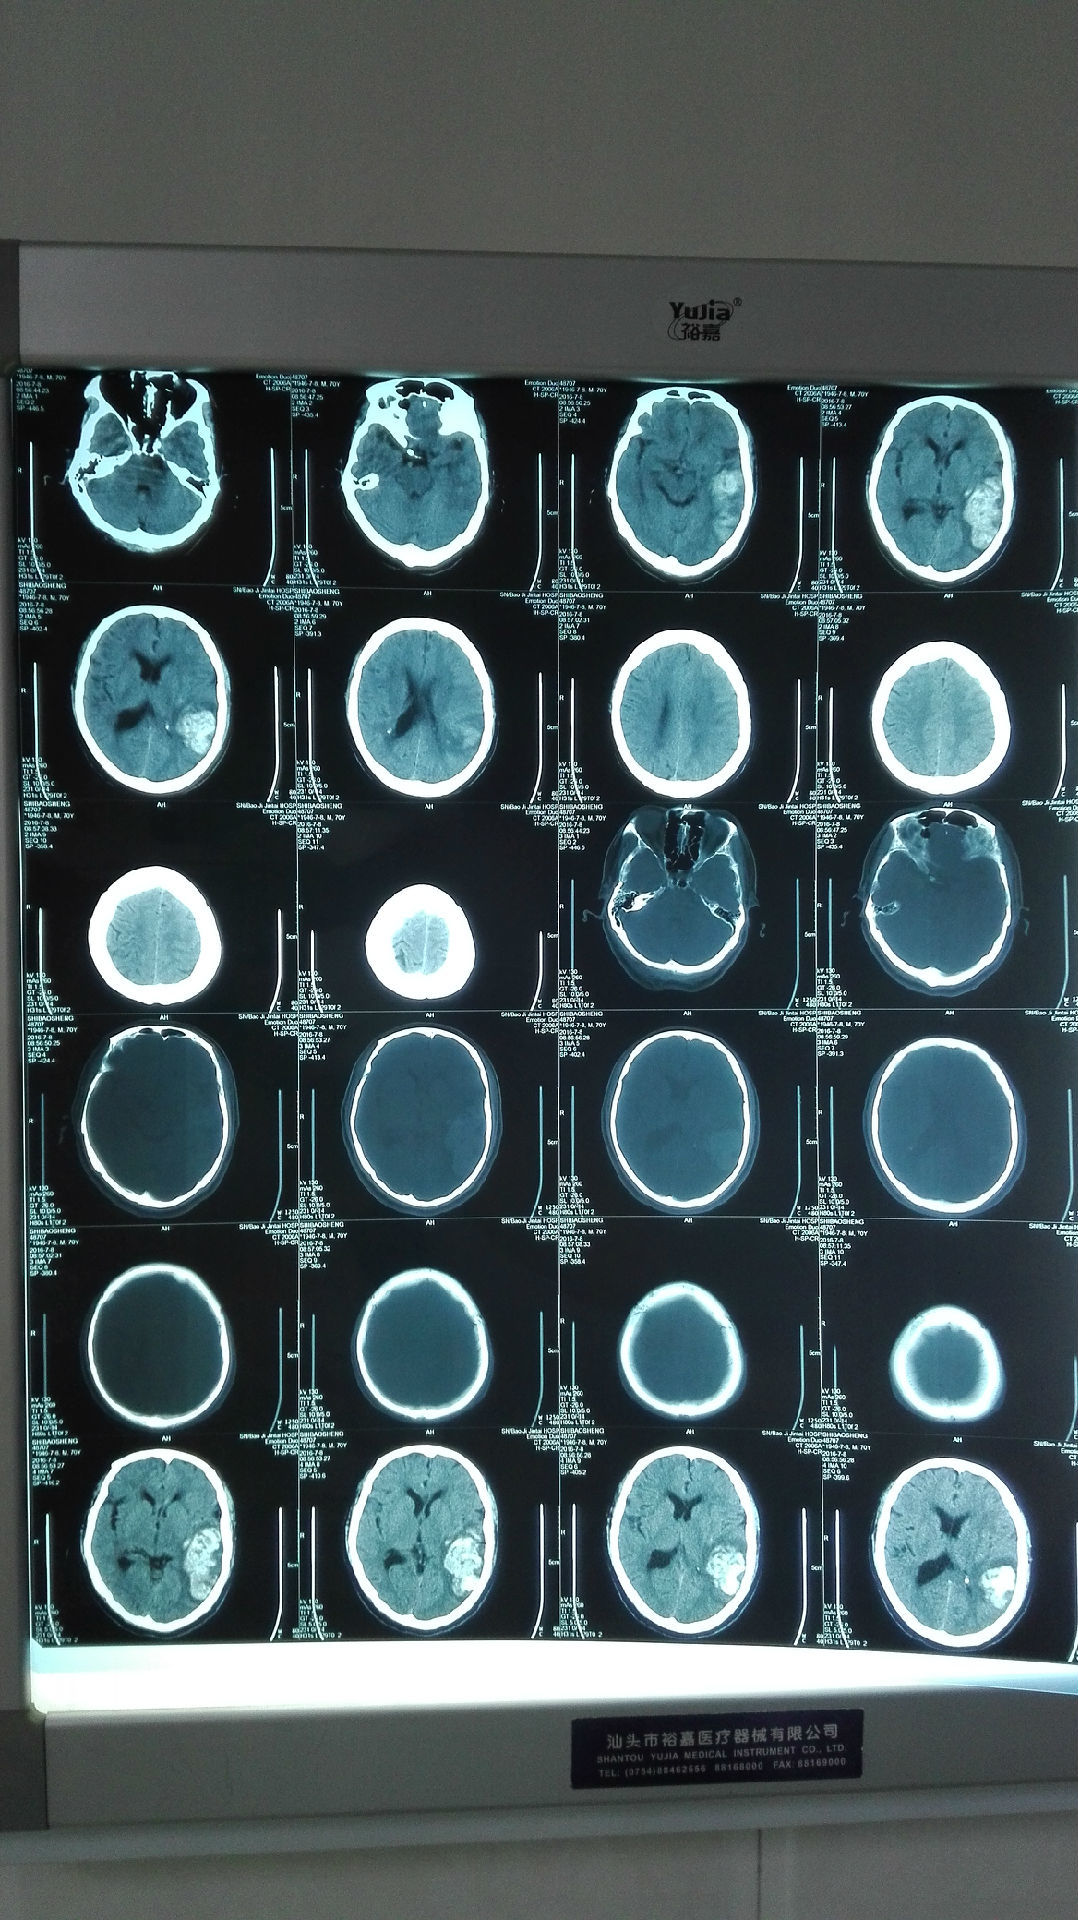

术前患者ct提示:小脑海绵状血管瘤

术中清除完血肿,见1x1cm3海绵状血管瘤,并仍在出血,一并切除.